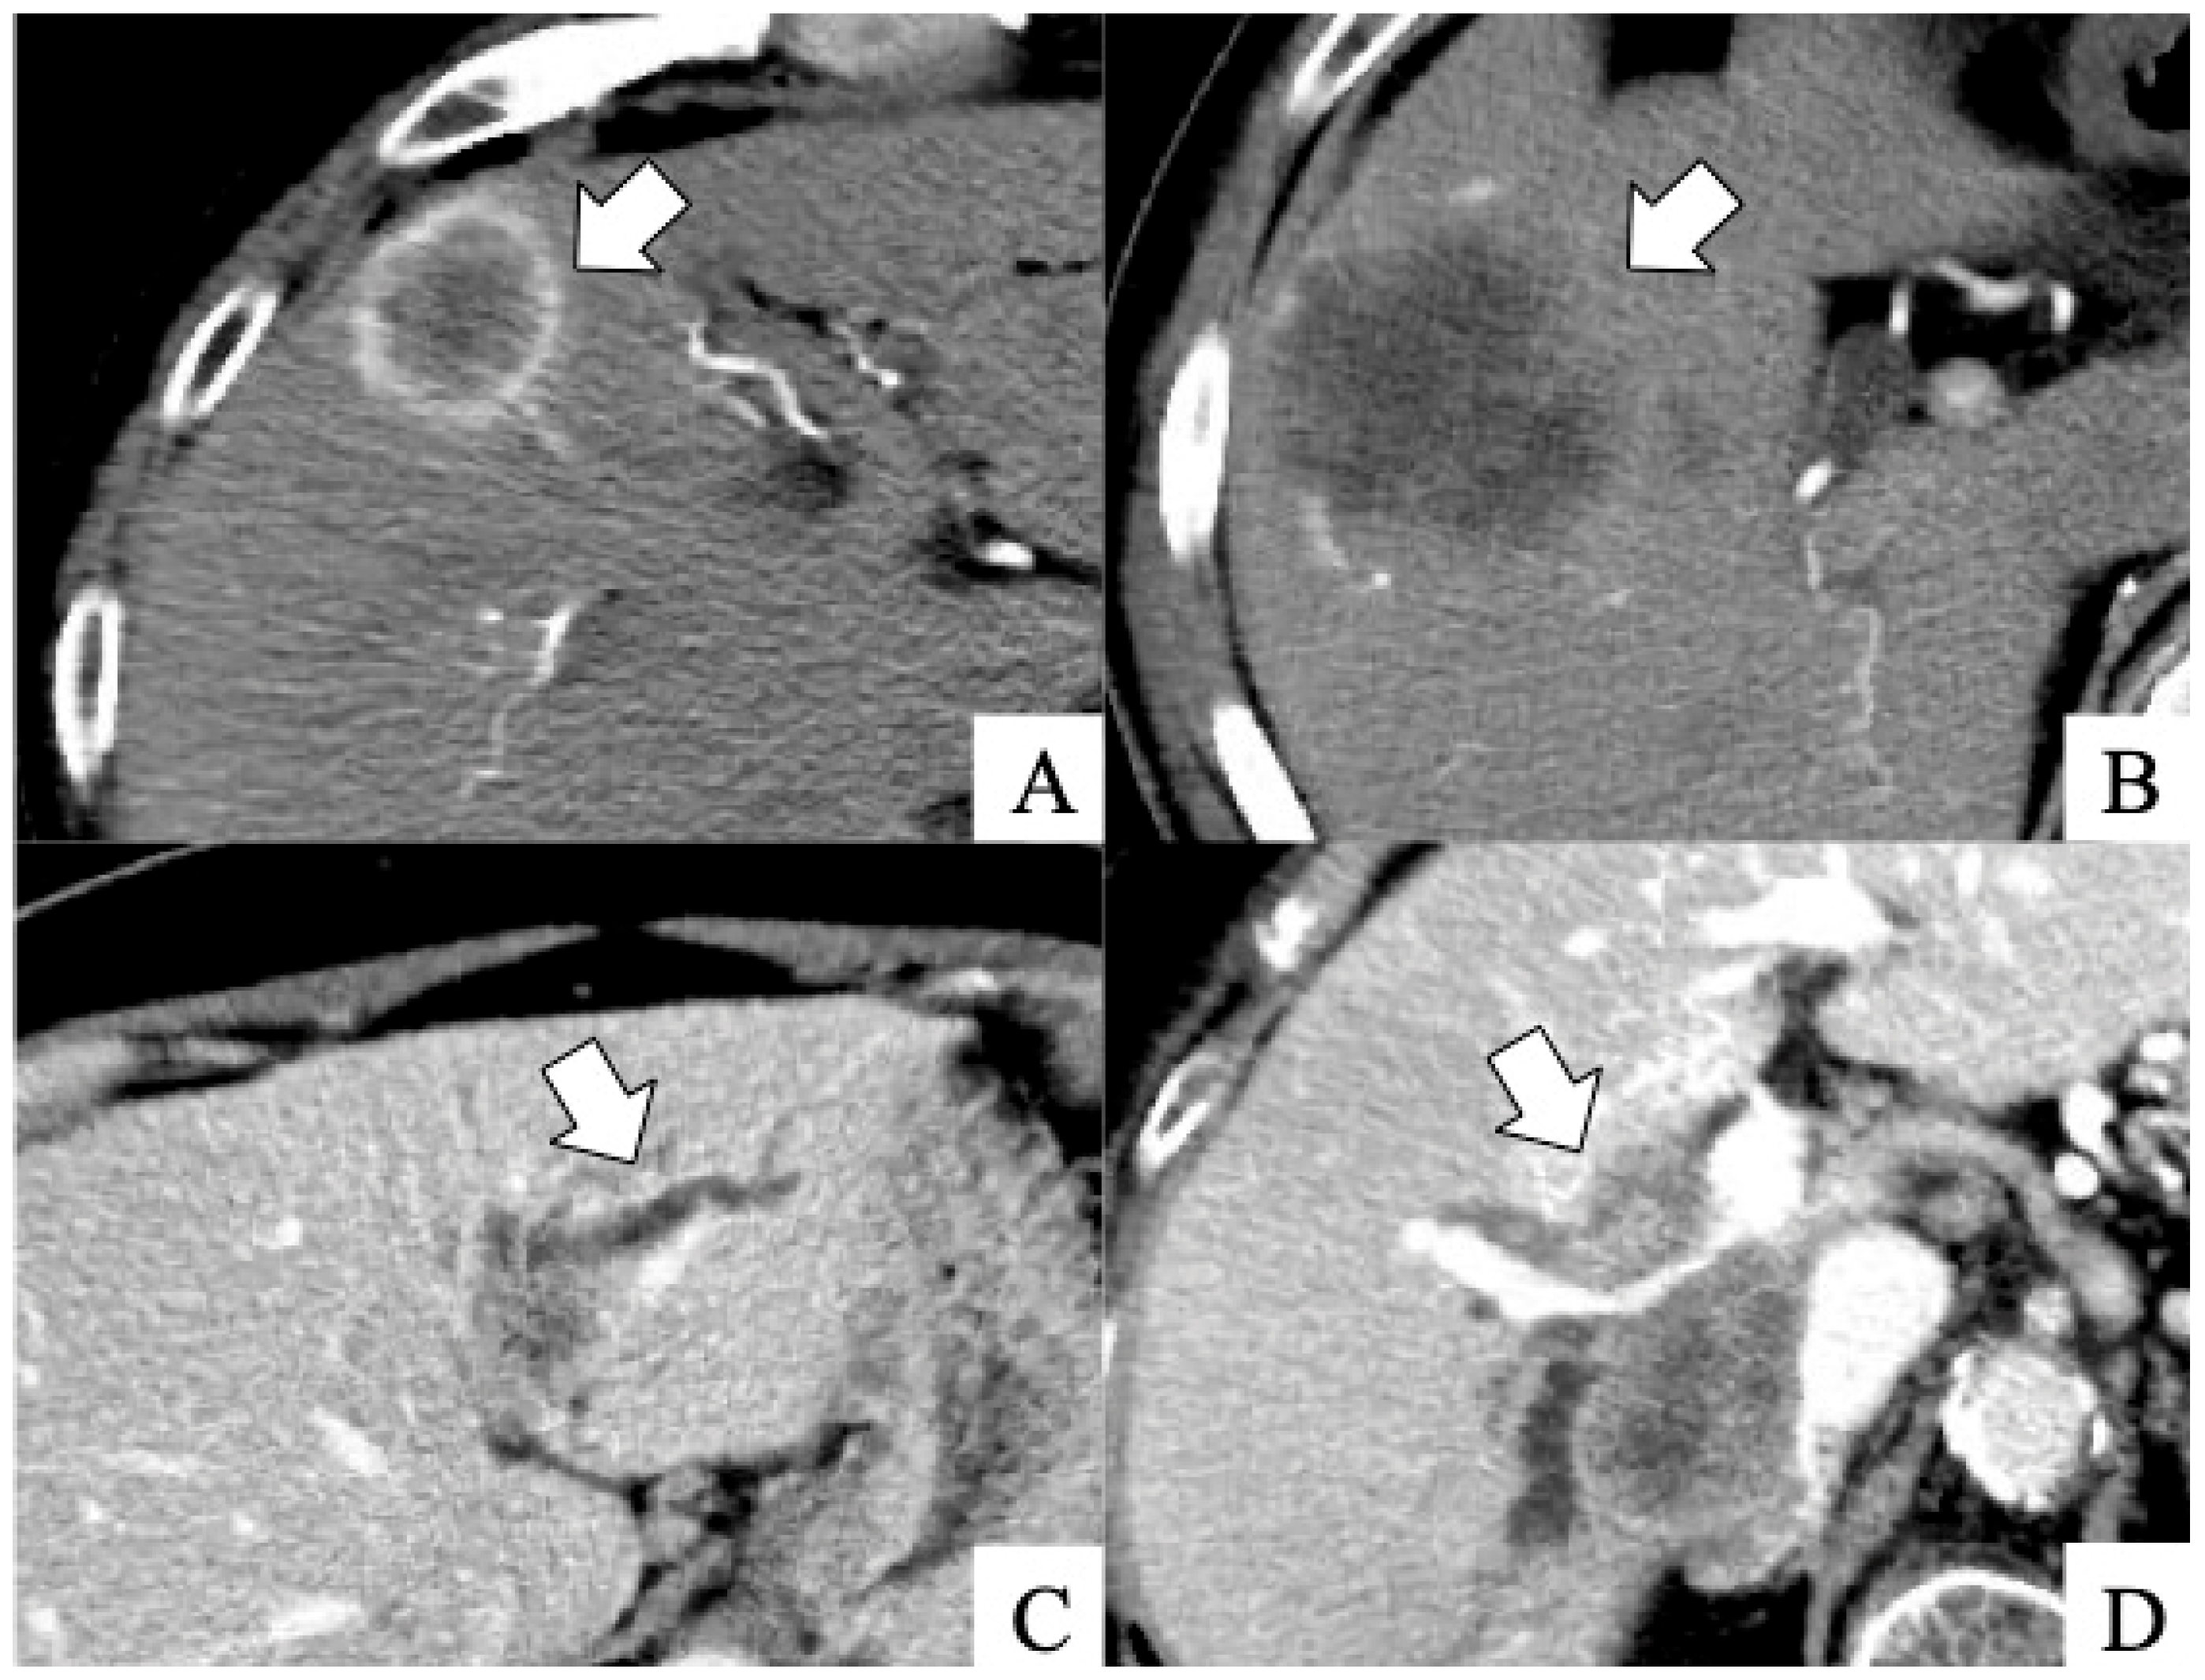

| Dynamic CT scan findings | |||

| Rim-type enhancement in the early phase, n | 51 | 23 | <0.001 |

| Absence of tumor enhancement in the early phase, n | 4 | 18 | <0.001 |

| Peripheral biliary dilatation due to tumor invasion, n | 8 | 39 | <0.001 |

| Penetrating Glisson’s vessel in the tumor, n | 8 | 39 | <0.001 |